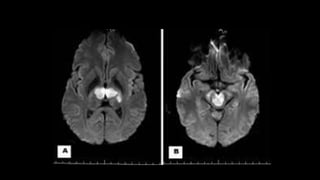

• #158 This is a c/o AOP INFARCTION . Axial DWI images shows diffusion restriction in bilateral paramedian thalamic and midbrain region – consistent with acute infarct.